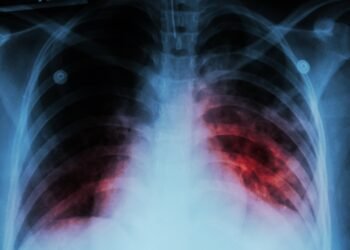

Aumentan casos graves de tuberculosis en Nuevo Laredo; reportan dos muertes

Nuevo Laredo, Tamaulipas.- El Hospital General de Nuevo Laredo ha atendido en lo que va de 2026 a pacientes con ...